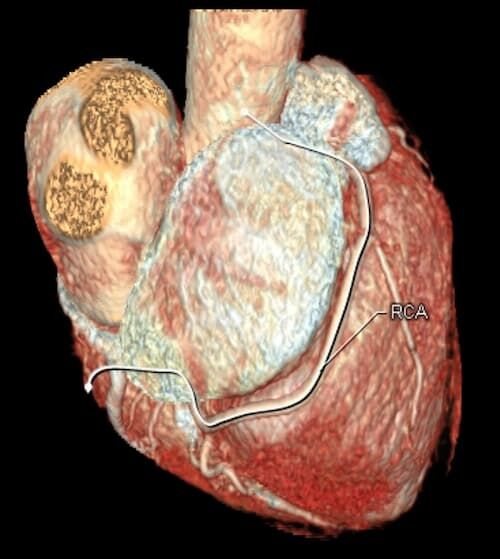

Herz

Durchführung am Standort im Diakonissenkrankenhaus

Die Computertomographie ermöglicht einen vielfältigen Einsatz. Es können Aufnahmen von Kopf bis Fuß in höchster Bildqualität erstellt werden. Eine Stärke der Methode liegt z. B. in ihrer Schnelligkeit. Deshalb wird sie häufig in der Notfalldiagnostik eingesetzt, aber auch bei der Darstellung von Körperbereichen, die ständig in Bewegung sind, wie z. B. die Lunge und das Herz. Außerdem eignet sie sich deshalb auch für die Untersuchung von schwer kranken, wenig belastbaren Patienten.

• mehrdimensionale Darstellung vasculärer Strukturen mit zahlreichen Auswertungstools